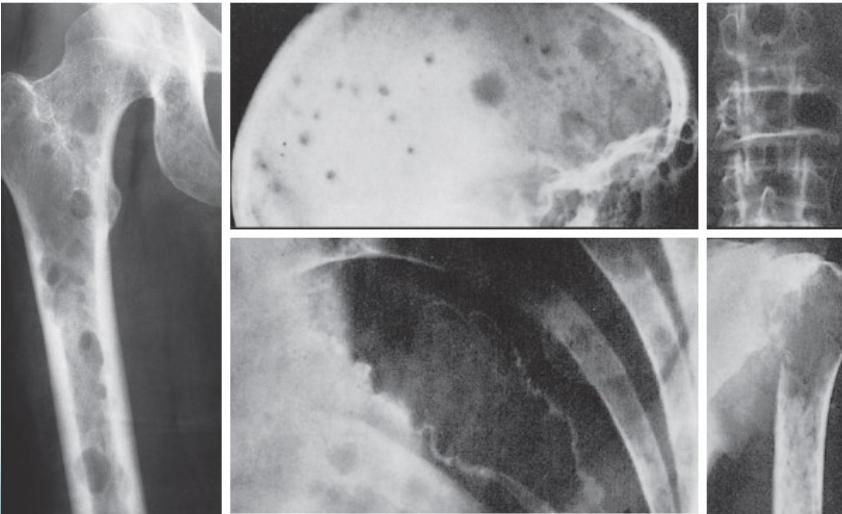

Radiological Features

- X-ray:

- Multiple punched-out lesions

- Osteoporosis & Vertebral compression fracture:

- If both present in a male >45: ? Myeloma

- Common sites:

- Skull, Prox. Femur, vertebrae

- Bone marrow biopsy